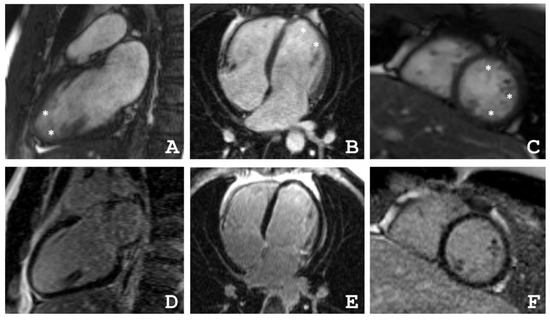

4.2. Cardiac Magnetic Resonance Imaging

| Patient | The Ratio NC/C in Segments | ||||||||||||||||

|---|---|---|---|---|---|---|---|---|---|---|---|---|---|---|---|---|---|

| 1 | 2 | 3 | 4 | 5 | 6 | 7 | 8 | 9 | 10 | 11 | 12 | 13 | 14 | 15 | 16 | 17 | |

| III-2 | 0 | 0 | 0 | 0 | 0 | 1.1 | 4.0 | 0 | 0 | 1.6 | 2.1 | 3.5 | 0 | 0 | 1.4 | 0 | 0 |

| III-4 | 1.2 | 0 | 0 | 0 | 1.2 | 2.2 | 1.1 | 0 | 0 | 3.8 | 3.0 | 3.0 | 4.9 | 3.3 | 3.5 | 2.8 | 5.9 |

| IV-3 | 3.3 | 1 | 0 | 0 | 0 | 0 | 3.5 | 2.5 | 1.1 | 0 | 0 | 1 | 8.3 | 8.3 | 6.3 | 8.3 | 10.5 |

| Patient | EDV | EF | Grothoff, [16] | Jacquier, % [17] | Petersen, [18] | |||

|---|---|---|---|---|---|---|---|---|

| Mass Index of NC, g/m² | NC/Myocardial mass, % | NC/C ≥ 3:1 in One Segment(1–3, 7–16) | NC/C ≥ 2:1 in 4–6th Segments | |||||

| III-2 | 77 | 31 | 12 | 20 | + | − | 20 | + |

| III-4 | 82 | 55 | 8 | 14 | + | + | 16 | + |

| IV-3 | 64 | 48 | 21 | 36 | + | − | 36 | + |